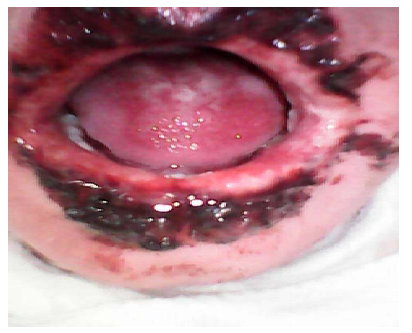

El examen bucal mostró lesiones costrosas y blanquecinas en labios y mucosas (Figura 3).